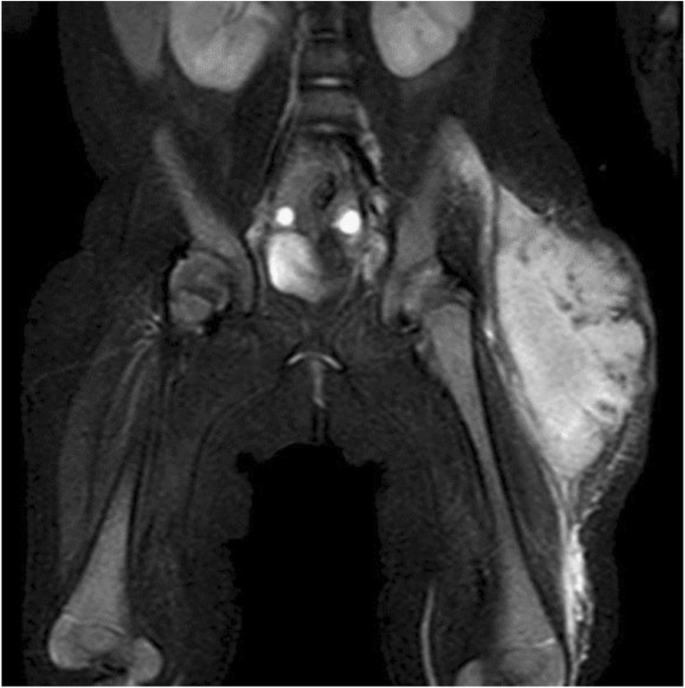

A 4-month-old girl was hospitalized with a swelling on her left thigh and an inability to move her left leg; she was afebrile. The patient was born by normal vaginal delivery after a full-term gestation and had no relevant medical history. The swelling of the left thigh appeared 1 week before hospitalization and gradually increased in size. The patient had received routine vaccination, including a second PCV-13 vaccination on her left thigh 1 month prior to hospitalization. After the vaccination, the patient did not have fever, and the injection site was clear of any signs of infection; therefore, she was not followed up. On examination, the patient appeared alert and well. She had normal vital signs (temperature, 36.1 °C; pulse, 152 beats per min; respiratory rate, 30 breaths per min; and oxygen saturation, 99%). The patient did not move her left leg and cried on touching it. An erythematous, tender, and firm, but not fluctuant, skin lesion measuring 8 × 7 cm was detected on her left thigh (Fig. 1). Laboratory investigations revealed leukocytosis (white blood cell count, 24.2 × 109 /L; 47% neutrophils, 42% lymphocytes); hemoglobin concentration, 11.6 g/dL; platelet count, 910 × 109 /L; and C-reactive protein level, 35.9 mg/L. Immunoglobulin (Ig) levels were as follows: IgG, 2,274 mg/dL; IgA, 99 mg/dL; and IgM, 99 mg/dL. The IgG subclasses, complement studies as well as neutrophil sterilizing and phagocytosis functions were normal. HIV screening showed negative results. Ultrasonographic imaging revealed a large subcutaneous hypoechoic fluctuant fluid-filled lesion measuring 8 × 7 × 4 cm (Fig. 2). There were no hypoechoic lesions in the abdominal organs. Magnetic resonance imaging revealed a large collection of subcutaneous fluid on the left thigh, with absence of other diseases such as osteomyelitis or pyomyositis (Fig. 3).